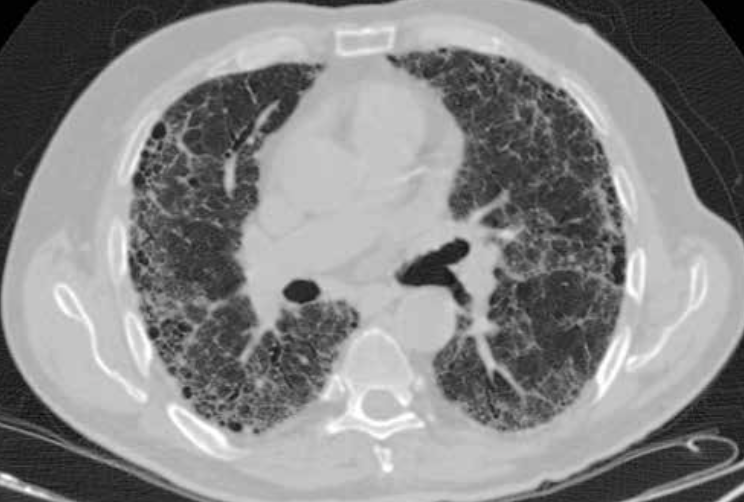

Principales utilidades de TC de alta resolución?

Imagen de TC de alta resolución que muestra fibrosis pulmonar.

Principales utilidades de TC de alta resolución son:

• Valorar el grado de afectación de enfermedades intersticiales pulmonares.

• En pacientes EPOC, para valorar el grado de enfisema y pequeñas zonas de atrapamiento aéreo.

• Determinar la gravedad y extensión de bronquiectasias.

• Valorar qué área es más rentable biopsiar.